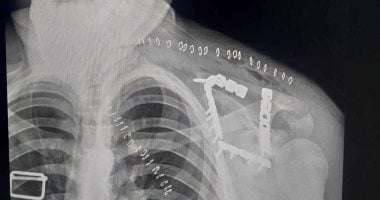

كان استقبل مستشفى التأمين الصحي بالفيوم شابًا يبلغ من العمر 17 عامًا، يعاني من كسر مفتت بعظمة لوح الكتف (Scapula)، وهي من الإصابات الدقيقة التي تتطلب مهارة عالية وتدخلًا جراحيًا متخصصًا.

خضع المريض لعملية جراحية معقدة استمرت نحو 4 ساعات تحت تأثير التخدير العام، تم خلالها رد وتثبيت الكسر بإستخدام الشرائح والمسامير.

شاب أصيب بكسر مفتت بلوح الكتف (1)